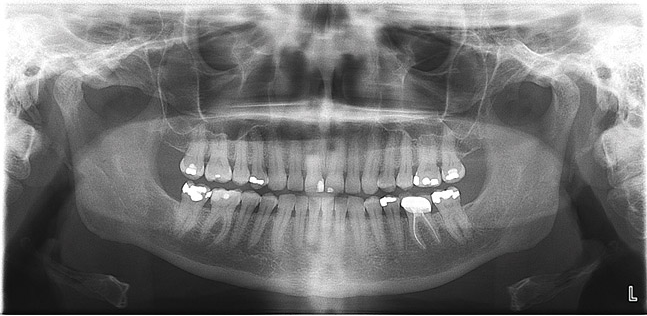

Panoramic

A digital panoramic radiograph (Figure 2) is indicated for circumstances in which intraoral imaging is not practical, as in patients who cannot open their mouths due to trismus or in those who cannot tolerate having a sensor or film in their mouth due to severe mucositis following radiation therapy for cancer. Advantages of panoramic imaging are that it quickly provides broad coverage of facial bones and teeth, it is convenient for both dental practitioner and patient, and is a helpful visual aid in patient education and case presentation.

Drawbacks of panoramic imaging are the cost—$25,000 to $85,00019—and that vertical beam angulation is not adjustable. Also, like a traditional panoramic machine, the digital unit requires dedicated operatory space, so there’s no space savings other than not needing a darkroom.